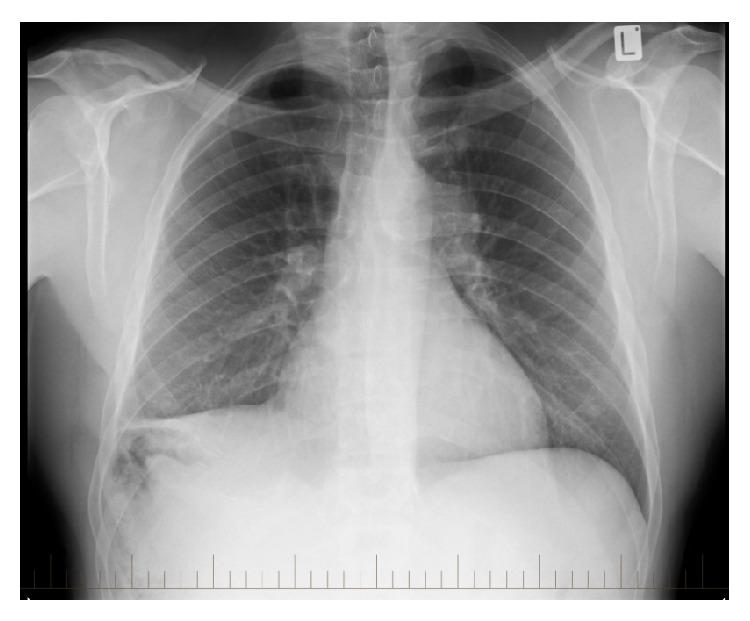

Blunt, nonpenetrating injuries of the thoracic aorta are uncommon and associated with a high mortality rate within the first hour. Aortic injury is missed in 1-2% of patients that survive to hospital, and a chronic thoracic aortic aneurysm may subsequently form. We present a case in which a chronic thoracic aortic aneurysm was diagnosed 29 years following a significant motor vehicle accident. We discuss the epidemiology, presentation, and management of this uncommon consequence of blunt, nonpenetrating aortic injury. Our case illustrates an important clinical lesson; a past medical history of trauma should not be overlooked at any patient assessment.